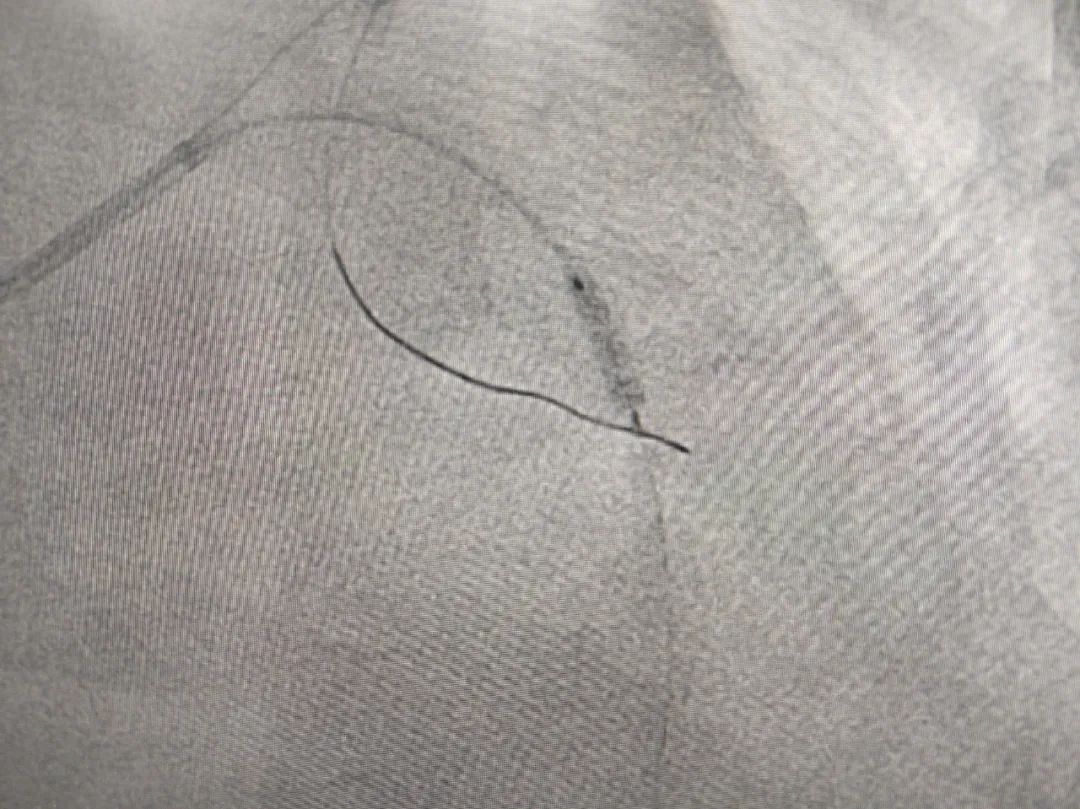

术中治疗造影

术前(左),术后(右)造影